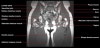

- Coronal section

T1 Allows for evaluation of both hips simultaneously even though the patient may be symptomatic in only one hip.

T2 allows for detection of abnormal fluid in both hips which may be seen in avascular necrosis, stress fractures, muscle tears or perilabral cysts.